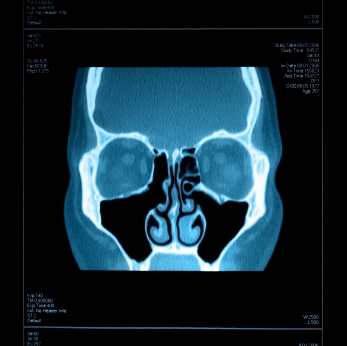

ДИАГНОСТИКА

Изучение истории болезни и медицинский осмотр не проводятся. Порой КТ или МРТ будет сделано.

Медицинские процедуры, проводимые при заболевании гайморит (синусит): Спиральная компьютерная томографияЛЕЧЕНИЕ И ПРОФИЛАКТИКА